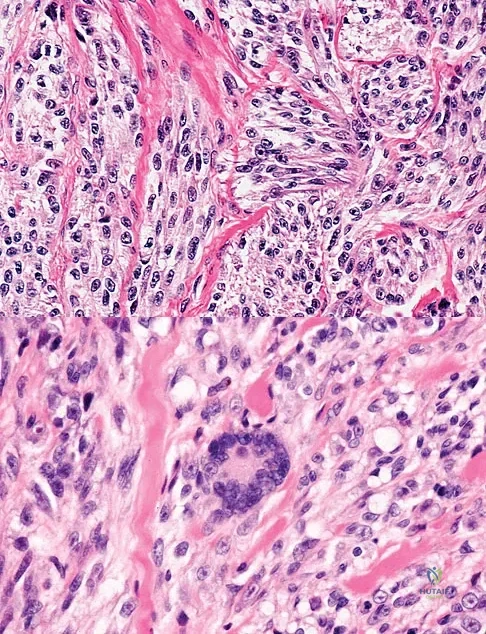

Question 18:

A 35-year-old man reports the development of a painful 2-cm nodule on his dorsal wrist over the past 3 years. A surgeon excised the lesion with a presumptive diagnosis of a ganglion cyst. Histology sections from the excision are shown in Figures 11a and 11b. What is the most likely diagnosis?

Options:

- Ganglion cyst

- Clear cell sarcoma

- Epithelioid sarcoma

- Epidermal inclusion cyst

- Synovial sarcoma

Correct Answer: Clear cell sarcoma

Explanation:

The histologic appearance of the soft-tissue lesion reveals compact nests of cells with a clear cytoplasm surrounded by a delicate border of fibrocollagenous tissue. There can be scattered multinucleated giant cells. This is consistent with a clear cell sarcoma, also called malignant melanoma of soft parts. This tumor is usually positive for S-100 and HMB45 (a melanoma-associated antigen). These tumors are frequently found around the foot and ankle. Similar to epithelioid sarcoma, it is usually intimately bound to tendons or tendon sheaths. Often the tumors are present for many years. The classic histologic appearance of this lesion differentiates it from the other choices. Enzinger FM, Weiss SW: Soft Tissue Tumors, ed 3. St Louis, MO, Mosby, 1995, p 913.